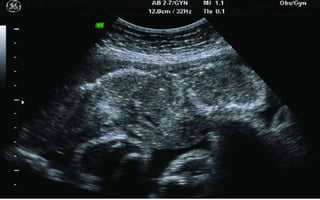

SECOND & THIRD TRIMESTER SCAN

• Bi-parietal Diameter (BPD)

• Head Circumference (HC)

• Femur Length (FL)

• Abdominal Circumference (AC)

• All can be of – or + 2 weeks